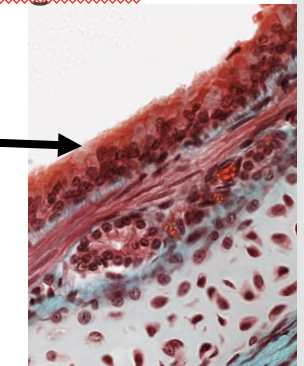

pathologische verschillen bij eczeem

epitheel:

hyperkeratose (verdikte hoornlaag)

parakeratose (celkernen in hoornlaag)

acanthose (verdikt epitheel)

spongiose (celbruggen

dermis:

verhoogd aantal lymfocyten (perivasculair

huidepitheel: wat w aangeduid

eczeem, spongiose